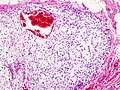

Dedifferentiated chondrosarcoma

Clinical:

- Abysmal to poor prognosis.

Features:[16]

- Poorly differentiated (mesenchymal) malignancy.

- Well-differentiated cartilaginous component.

DDx:

- Undifferentiated pleomorphic sarcoma - no cartilaginous component.

- Other dedifferentiated tumours, e.g. dedifferentiated liposarcoma, with a minimal differentiated component.